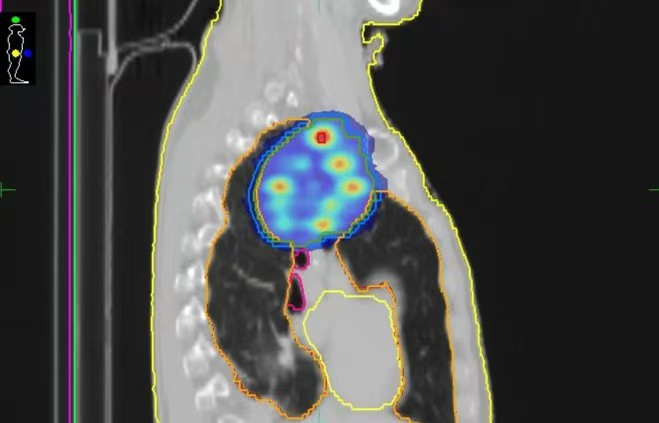

10月27日,南华大学附属第二医院肿瘤中心成功为一名肺癌巨大肿块患者实施了空间分割放疗(SFRT)。这项在双能CT多模态影像引导下完成的技术,不仅是南华大学附属第二医院的首例实践,更一举填补了湖南省在该领域的技术空白,标志着该院肿瘤放疗水平正式迈入“精准制导”新时代。

面对位置特殊、体积巨大的复杂肿瘤,传统的手术、化疗与放疗往往效果有限。传统放疗如同“地毯式轰炸”,在杀伤癌细胞的同时,难以避免地对周围正常组织造成损伤。而此次应用的“空间分割放疗”技术,则实现了从“面”到“点”的跨越,堪称放疗领域的“精确制导系统”。它通过在肿瘤内部同步创建高剂量“峰区”和低剂量“谷区”,形成精密的剂量分布:“峰区”负责对核心顽固区域实施“重点打击”,直接而强力地杀伤肿瘤细胞;“谷区”则在保护正常组织的同时,巧妙刺激免疫反应。二者协同作用,在最大化杀伤肿瘤的同时,犹如为周围的正常肺组织、心脏、脊髓等重要器官穿上“防护甲”,不仅能显著减轻治疗副反应,还能通过产生的“免疫激活效应”触发全身抗肿瘤免疫,为后续联合免疫治疗奠定基础,甚至产生“1+1>2”的协同效果,为以往因肿瘤过大、位置过险而无法耐受放疗的患者提供了新的治疗希望。